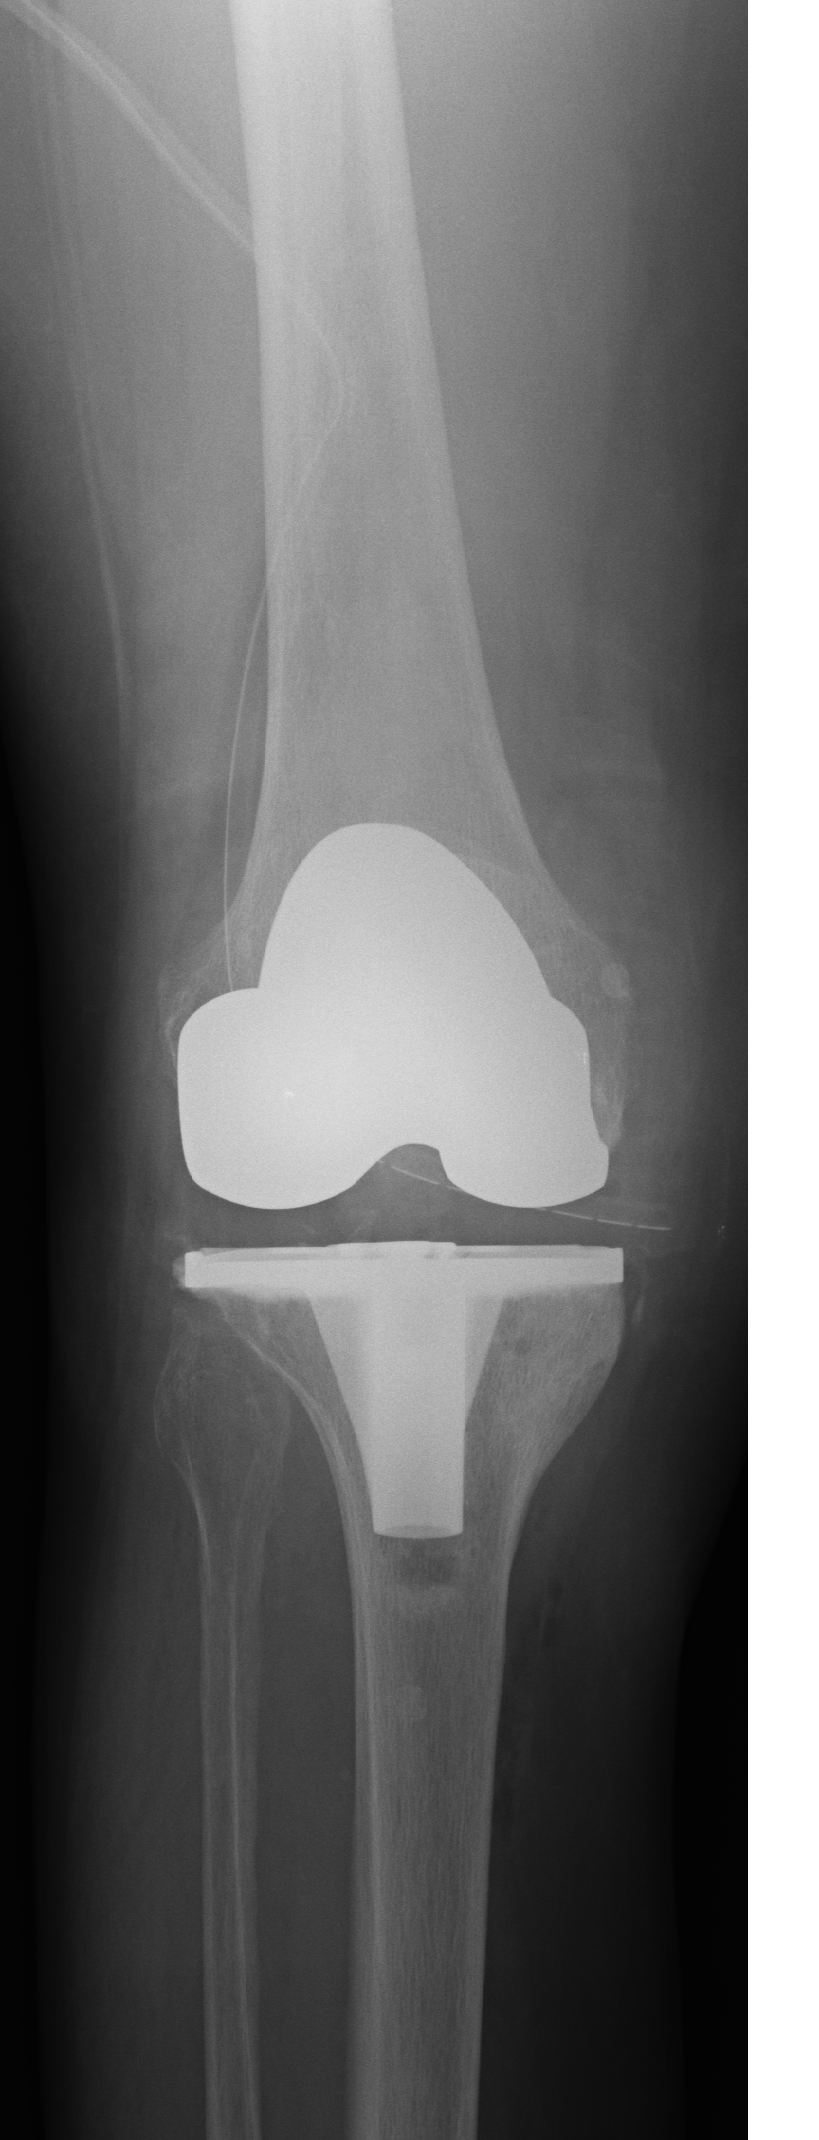

- Ендопротезиране на колянна и тазобедрена става

Основно лекувам заболявания на тазобедрена и колянна става чрез минимално инвазивно ендопротезиране, следтравматични и дегенеративни нарушения на ръката и китката и халукс валгус (популярен като „кокалчета на краката”).